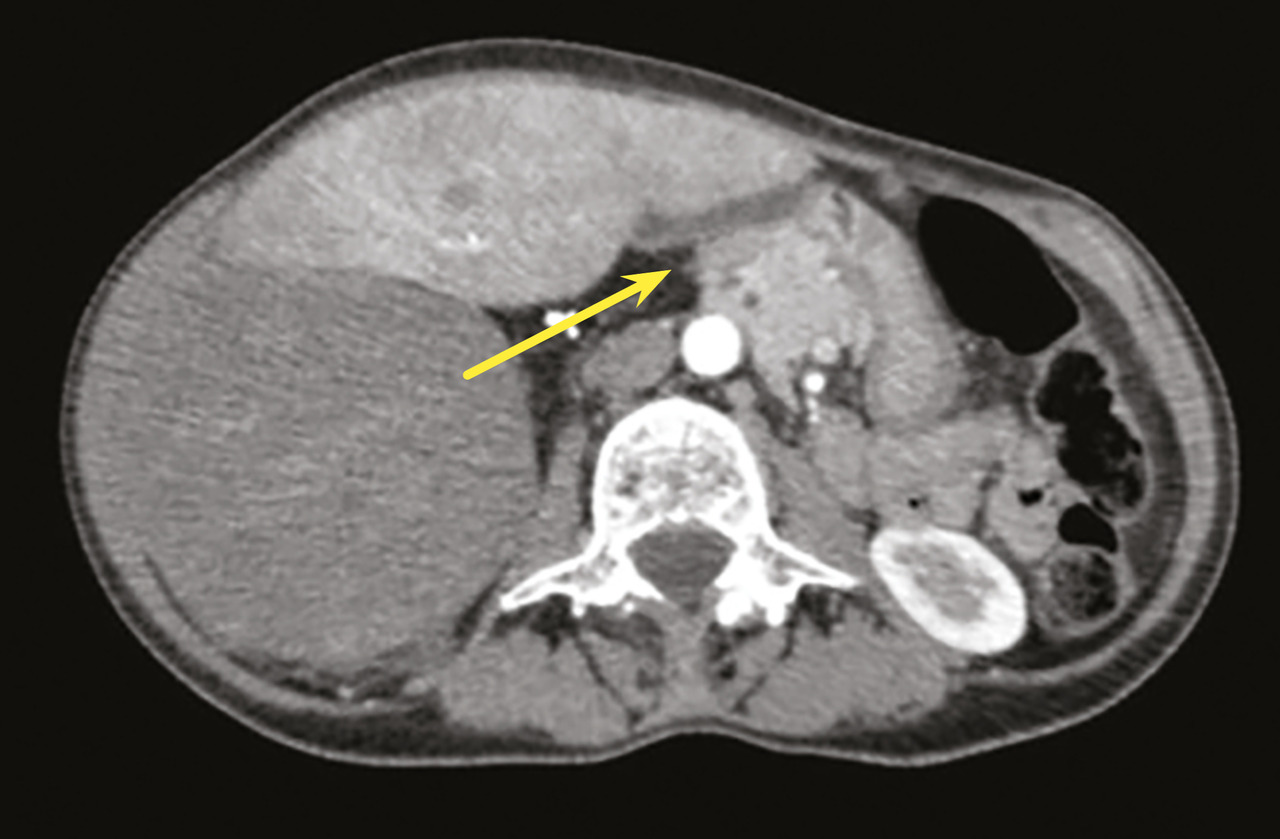

Au niveau abdominal, les signes sont fréquemment une augmentation du périmètre abdominal ou des troubles digestifs ; le patient s’est parfois mis au régime, avec pour conséquence une dénutrition, qui doit être dépistée avant la chirurgie.7 Le scanner abdominal est le premier examen à réaliser. Il convient d’être vigilant à l’égard de l’extension des tumeurs abdominales, en particulier rétropéritonéales, dans les défilés anatomiques (arcade crurale, trous de conjugaison, hiatus œsophagien), source de reliquats macroscopiques.8 De même, la composante bien différenciée (qui ressemble à de la graisse normale) d’un liposarcome rétropéritonéal est très souvent sous-estimée, ce qui peut engendrer des exérèses incomplètes, à l’insu d’un opérateur non spécialisé (fig. 1). Il est essentiel de considérer le déplacement des organes intra-abdominaux pour voir l’ensemble de la tumeur.9 Il est nécessaire de vérifier l’absence d’atteinte osseuse associée, qui modifie la classification diagnostique et donc les modalités thérapeutiques, notamment le choix du chirurgien expert.